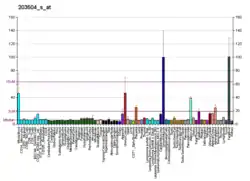

It was discovered that a mutation in the ABCA1 protein is responsible for causing Tangier disease by several groups in 1998. Gerd Schmitz's group in Germany[6] and Michael Hayden's group in British Columbia[7] were using standard genetics techniques and DNA from family pedigrees to locate the mutation. Richard Lawn's group at CV Therapeutics in Palo Alto, CA used cDNA microarrays, which were relatively new at the time, to assess gene expression profiles from cell lines created from normal and affected individuals.[8] They showed cell lines from patients with Tangier's disease showed differential regulation of the ABCA1 gene. Subsequent sequencing of the gene identified the mutations. This group received an award from the American Heart Association for their discovery.[9] Tangier disease has been identified in nearly 100 patients worldwide, and patients have a broad range of biochemical and clinical phenotypes as over 100 different mutations have been identified in ABCA1 resulting in the disease.[10]

Mutations in this gene have been associated with Tangier disease and familial high-density lipoprotein deficiency. ABCA1 has been shown to be reduced in Tangier disease which features physiological deficiencies of HDL.[22][23] Leukocytes ABCA1 gene expression is upregulated in postmenopausal women receiving hormone replacement therapy (HRP).[24] ABCA1 expression is also upregulated in tumor-associated astroctytes surrounding glioblastoma brain tumors, and is important to the tumor progression. [25][26]